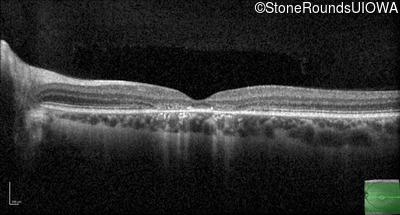

Optical Coherence Tomography - Right - 20/50 -1

Exemplar / OCT Stack

Optical Coherence Tomography - Left - 20/50 +2